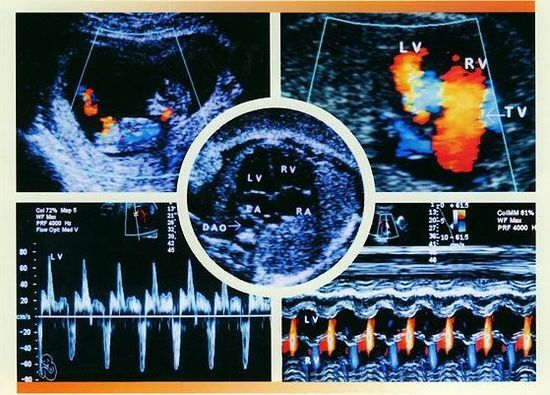

2、先进产检设备:贵阳和谐阳光医院引进的胎儿心脏彩超,对孕妇产前检查、各种先天性疾病的诊断,是目前上较为先进、科学的超声诊断仪器。